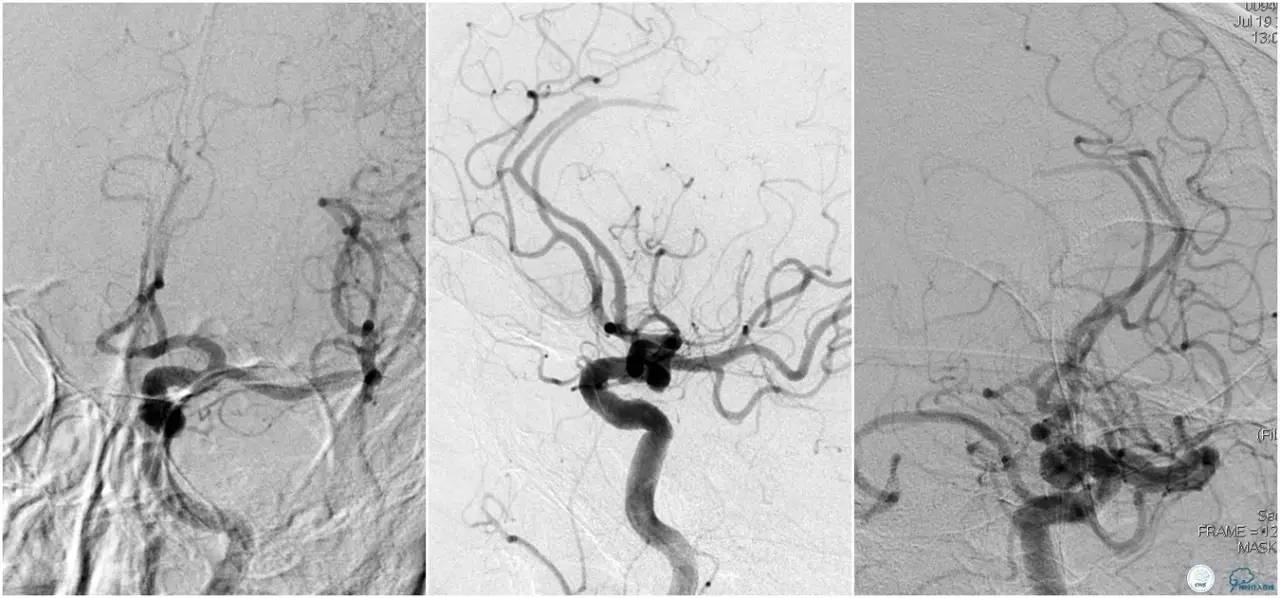

6F Envoy置于左侧颈内动脉C3段,选用Solitaire-FR 4*20mm支架释放于右侧大脑前动脉取栓1次,血流达TICI 2b。

Solitaire-FR 4*20mm支架释放于左侧大脑前动脉取栓1次,取出少许血栓重复造影左侧大脑前动脉胼周动脉开口后,右侧大脑前动脉A2段以远未显影,考虑栓子逃逸。

选用Solitaire-FR 4*20mm支架分别于右侧大脑前动脉A2-A3段,左侧胼周动脉,右侧胼周动脉取栓3次。

双侧大脑前动脉完全显影,TICI 3级,TOR 261min。